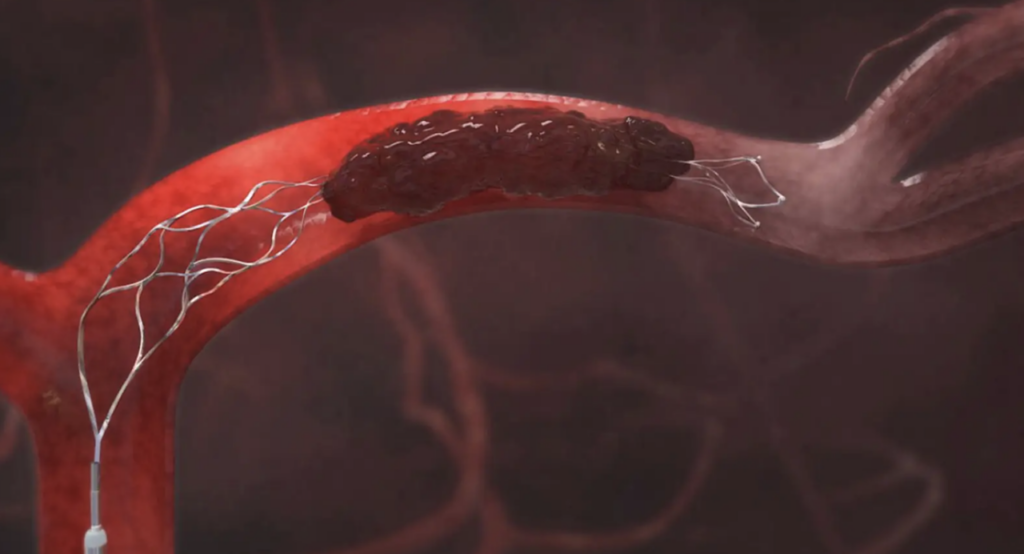

Lấy huyết khối bằng dụng cụ

Cho đến hiện tại, kỹ thuật lấy huyết khối cơ học là phương pháp điều trị cơ bản, được sử dụng kết hợp ngay sau khi dùng thuốc tiêu sợi huyết tĩnh mạch (với cửa sổ 4,5 giờ và không có chống chỉ định rt-PA) hoặc điều trị đơn thuần khi bệnh nhân tới cơ sở y tế ngoài cửa sổ 4,5 giờ sau khi đột quỵ não do tắc mạch lớn.

Từ năm 2018, thành công của nghiên cứu DAWN và DEFUSE 3 đã giúp mở rộng cửa sổ điều trị đột quỵ thiếu máu não cấp bằng dụng cụ cơ học từ 6 giờ lên đến 24 giờ ở một số bệnh nhân phù hợp các tiêu chuẩn lựa chọn.